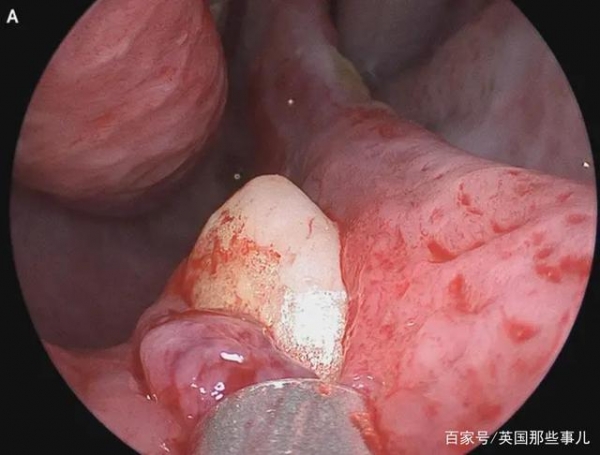

做鼻镜时,医生们先是发现A有鼻中隔偏曲的问题,也就是鼻中隔骨或软骨偏移到一侧或两侧的现象,会引起呼吸不畅。

继续检查时,医生们在鼻中隔后方发现一个“坚硬、不会压痛、白色的异物”,仔细辨认之后,他们确认这是一颗牙齿。这颗牙齿约有15毫米长,谁都不知道它为啥会长在鼻孔里,A的面部没有受过任何创伤,也看不出任何异常,医生找不到病因。